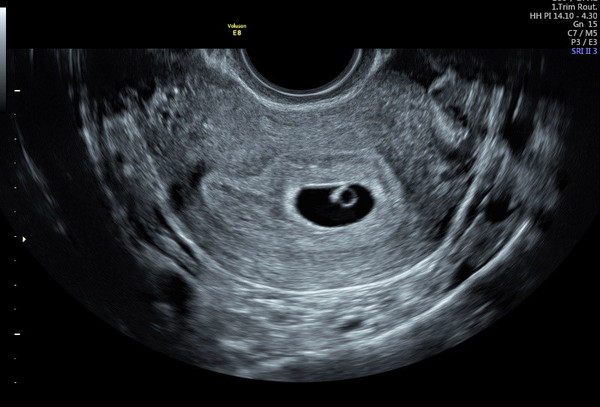

tigger2022 · 25/03/2022 13:57

@sarahj878 - I had a scan yesterday at 6 weeks and was able to see gestational sac, and the yolk sac, foetal pole, and also the heart pulsing. The baby looked like an engagement ring! This is the zoomed out image (zoomed in was visible and you can see the heart beating, but it's very low focus).